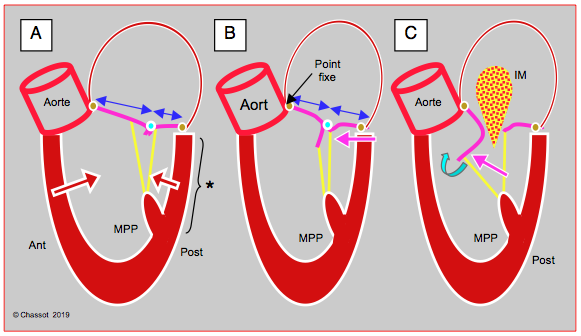

Mais si la cavité du VG se rétrécit au point que la paroi postéro-basale se déplace vers l’avant, le point de coaptation de la mitrale avance en direction de la chambre de chasse du VG (CCVG); l’occlusion n’a plus lieu sur le bord distal des feuillets mais entre l'extrémité du feuillet postérieur et le corps du feuillet antérieur. La partie distale de ce dernier flotte alors dans la cavité du VG, et l'élévation de la pression intraventriculaire la repousse antérieurement en direction de la CCVG. Par effet Venturi, elle est ensuite aspirée dans la CCVG, qu'elle occlut plus ou moins complètement. C’est le SAM (systolic anterior motion), qui survient en méso-systole (Figure 27.5) [4,17].

Figure 27.5 : Obstruction dynamique de la CCVG. A : situation normale. Le point de coaptation des feuillets mitraux est situé au tiers postérieur du diamètre antéro-postérieur (flèches bleues); en systole, la course radiaire de la paroi postéro-basale (*) est plus faible que celle de la paroi antéro-latérale; elle est activée électriquement en dernier. B: si le VG devient très petit par hypovolémie, la paroi postérieure avance en direction de la CCVG (flèche violette), parce que la zone antérieure est la jonction mitro-aortique qui est un point fixe (trigone fibreux); le point de coaptation est alors projeté vers la CCVG. En protosystole, la coaptation a lieu entre l'extrémité du feuillet postérieur et le corps du feuillet antérieur, dont la partie distale se retrouve flottant dans le VG et non en application contre le feuillet postérieur. C : en mésosystole, la pression intraventriculaire pousse le feuillet antérieur en direction de la CCVG (flèche violette) où l'éjection a commencé; celui-ci est alors aspiré par effet Venturi (flèche bleu pâle) et vient bloquer la CCVG (SAM: systolic anterior motion). Le débit aortique baisse soudainement, et la réouverture de la valve mitrale provoque une insuffisance méso-télésystolique (IM). MPP: muscle papillaire postérieur.

Mais si la cavité du VG se rétrécit au point que la paroi postéro-basale se déplace vers l’avant, le point de coaptation de la mitrale avance en direction de la chambre de chasse du VG (CCVG); l’occlusion n’a plus lieu sur le bord distal des feuillets mais entre l'extrémité du feuillet postérieur et le corps du feuillet antérieur. La partie distale de ce dernier flotte alors dans la cavité du VG, et l'élévation de la pression intraventriculaire la repousse antérieurement en direction de la CCVG. Par effet Venturi, elle est ensuite aspirée dans la CCVG, qu'elle occlut plus ou moins complètement. C’est le SAM (systolic anterior motion), qui survient en méso-systole (Figure 27.5) [4,17].

Figure 27.5 : Obstruction dynamique de la CCVG. A : situation normale. Le point de coaptation des feuillets mitraux est situé au tiers postérieur du diamètre antéro-postérieur (flèches bleues); en systole, la course radiaire de la paroi postéro-basale (*) est plus faible que celle de la paroi antéro-latérale; elle est activée électriquement en dernier. B: si le VG devient très petit par hypovolémie, la paroi postérieure avance en direction de la CCVG (flèche violette), parce que la zone antérieure est la jonction mitro-aortique qui est un point fixe (trigone fibreux); le point de coaptation est alors projeté vers la CCVG. En protosystole, la coaptation a lieu entre l'extrémité du feuillet postérieur et le corps du feuillet antérieur, dont la partie distale se retrouve flottant dans le VG et non en application contre le feuillet postérieur. C : en mésosystole, la pression intraventriculaire pousse le feuillet antérieur en direction de la CCVG (flèche violette) où l'éjection a commencé; celui-ci est alors aspiré par effet Venturi (flèche bleu pâle) et vient bloquer la CCVG (SAM: systolic anterior motion). Le débit aortique baisse soudainement, et la réouverture de la valve mitrale provoque une insuffisance méso-télésystolique (IM). MPP: muscle papillaire postérieur.